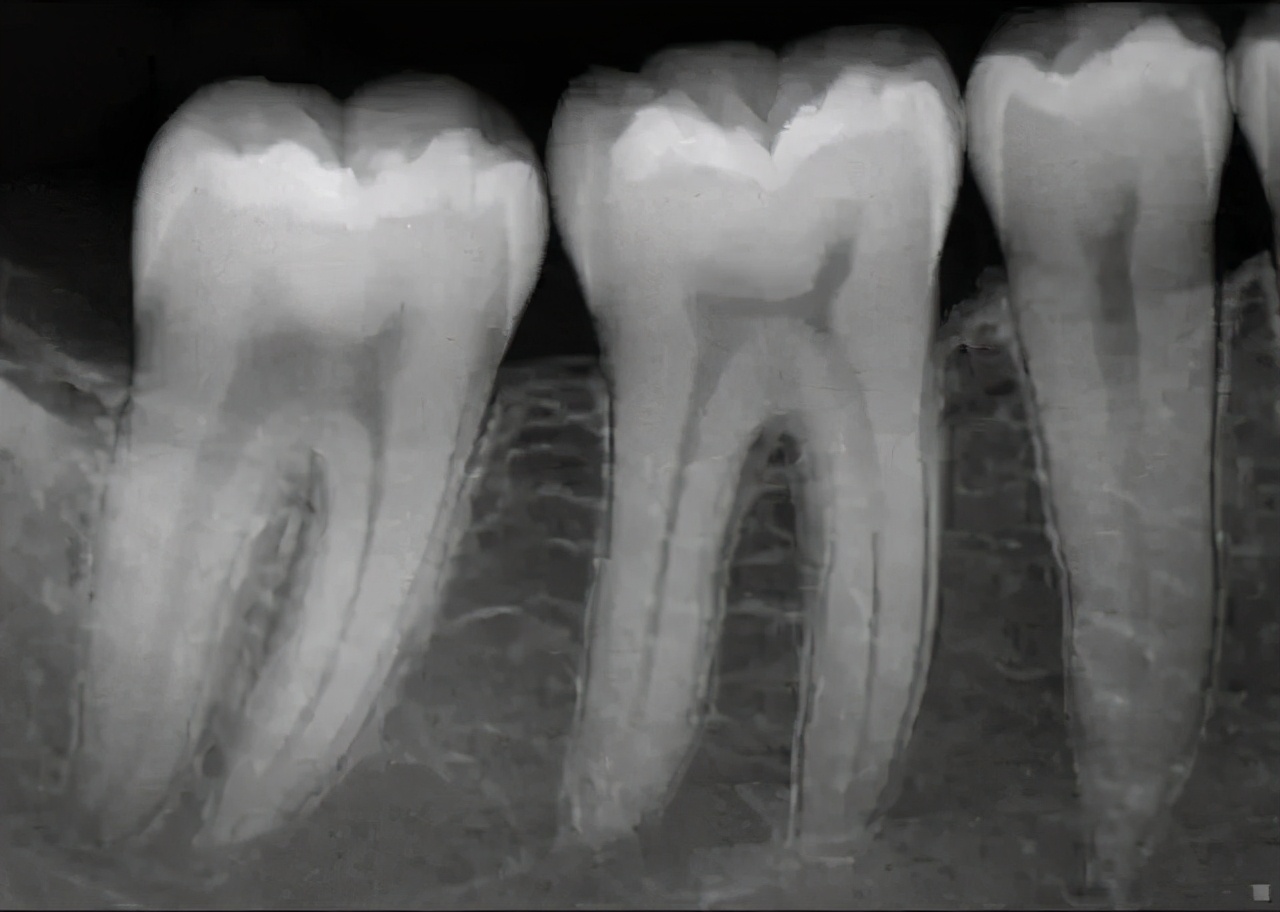

(3)小牙片

小牙片

以检查单颗牙齿为目的,一般图像上可显示2~4颗牙齿,能观察到牙根的情况,所以牙医们要检查单颗牙齿时,往往会选择拍摄小牙片。